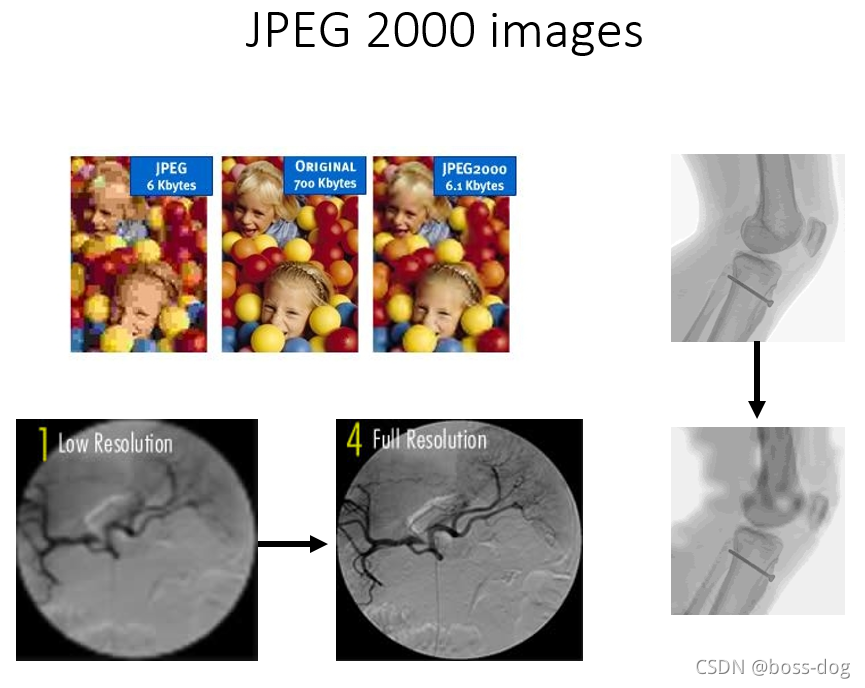

JPEG 2000 符合无损压缩。